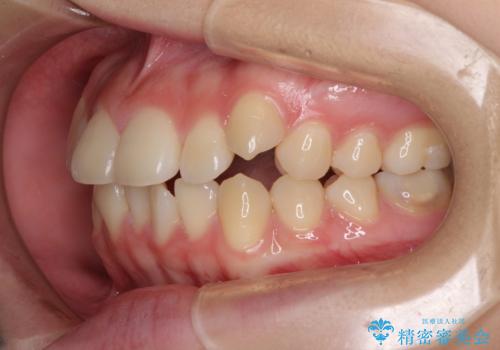

カリエール・ディスタライザーとインビザラインを用いた八重歯の改善

- 前歯の叢生と上顎左右の八重歯を気にして来院された患者様です。

奥歯の咬み合わせを見ると、左側は上顎が下顎に対して相対的に前方にあり、上下の前歯が接触していない状態でした。

咬み合わせを改善するためには、左側上顎臼歯を後方に移動させた咬み合わせにする必要があります。

インビザライン単体で改善することも可能性もありますが、インビザライン単体で達成する可能性が低いと考えられたため、カリエール・ディスタライザーという補助装置を併用して、より確実性を上げることとしました。

奥歯の咬み合わせを改善しながら、並行してインビザラインで歯列を整えることとしました。

カリエールディスタライザーを併用したことで、左側臼歯の咬み合わせを確実に改善させることができました。